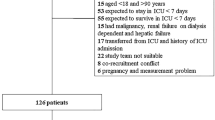

This is a retrospective analysis of prospectively collected data from 255 screened consecutive patients with nontraumatic SAH admitted to the neurocritical care unit of a tertiary referral center between April 2010 and November 2016. The study was approved by the ethics committee of the Medical University of Innsbruck (AN3898 285/4.8). Informed consent was obtained from all patients according to federal regulations. Inclusion criteria were the diagnosis of nontraumatic SAH, patient age above 18 years, and the availability of noncontrast enhanced head CT scans performed on admission and at least one performed 5–9 days or 12–16 days after admission. Patients were excluded if they were admitted to the neurocritical care unit 2 or more days after the hemorrhage, if they were transferred to another unit within 7 days of admission, and if the available CT scans were of insufficient quality for the measurement of temporal muscle volume.

Of 255 screened consecutive patients with nontraumatic SAH, 98 didn’t meet inclusion criteria, 33 were excluded due to insufficient quality of cerebral CT scans, 12 were excluded due to early transfer to another ward, and 2 were excluded due to late admission, leaving 110 patients for final analysis.